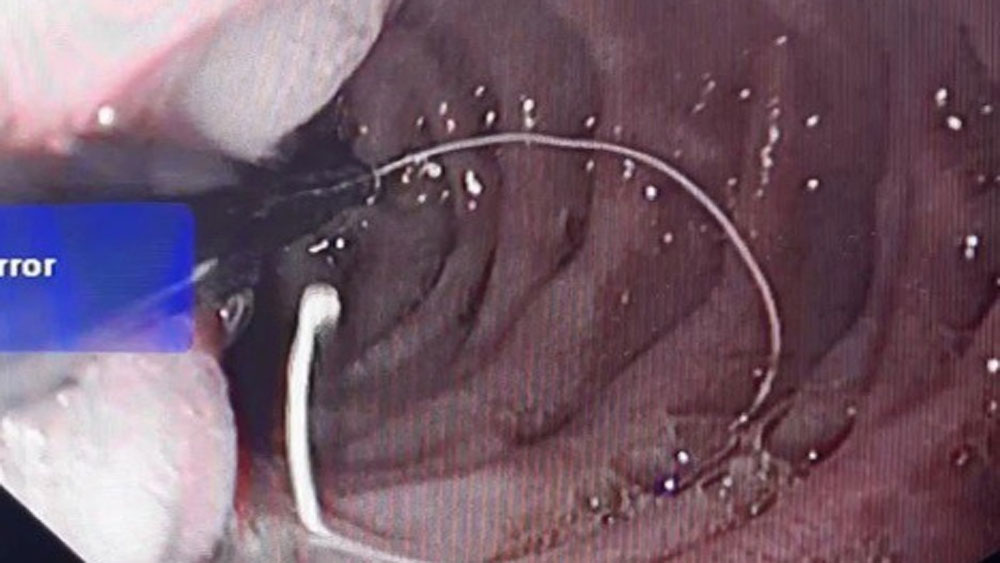

Chiếc kim kèm đoạn cước được các bác sĩ nội soi lấy ra. |

Các bác sĩ tiến hành nội soi cấp cứu và gắp ra một chiếc kim khâu kèm theo đoạn chỉ cước dài 25cm nằm ở phần D2 tá tràng. Quá trình thực hiện nội soi chỉ diễn ra trong 6 phút. Sau nội soi, cháu được theo dõi trong thời gian ngắn, ổn định về sức khoẻ, các bác sĩ cho cháu xuất viện trong ngày.